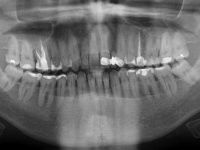

Fifty year old male patient, non-smoker. Carries a Maryland Bridge replacing tooth 2.2. "Maryland wings" are metallic and the dental surfaces in contact with them are infiltrated. Tooth 2.1 had a feldspathic ceramic veneer covering the vestibular surface. Tooth 1.2 presented a feldspathic ceramic veneer with exposed cervical margin. The edentulous space corresponding to tooth 2.2 is narrow and tall. Patient presents an open anterior bite, good oral hygiene and reasonable periodontal health.

A two element bridge was suggested, using tooth 2.1 as abutment and tooth 2.2 as cantilever pontic. Cantilever bridge with ceramic-coated Zr infrastructure.